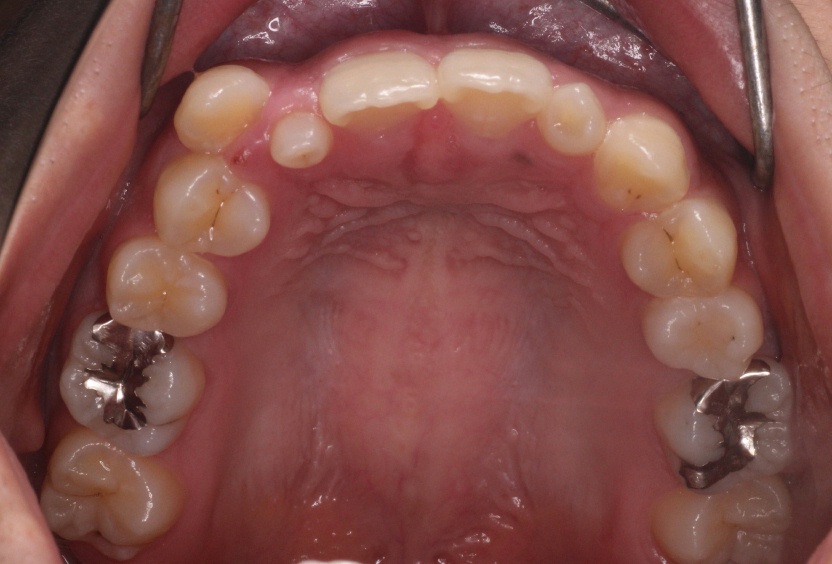

ソフトウェアが決定した通りに最適アタッチメントが歯牙唇側面(表側)の1カ所に設置され(下図のピンクのポッチ)、

アライナーの舌側面に第二のフォースを生み出すため(赤丸)、

アライナーにプレッシャーポイントが加工させる。(アライナーが一部くぼんでいる)

二つの機能が組み合わさり、複雑な3次元移動に適したフォースシステムが生み出されます。

ソフトウェアで可能となったこの最適アタッチメントは、上顎側切歯の3次元移動を目的にしており、

マルチプレーン挺出用アタッチメントと呼ばれています。